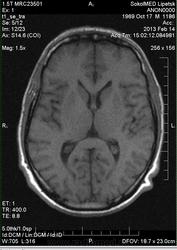

А чем можно объяснить гиперинтенсивный МР-сигнал по Т1ВИ и Т1 с жироподавлением, характерный для метгемоглобина?

Очень часто, независимо от возраста, в задних рогах встречаются обызвествления. Иногда они видны и на обычной краниограмме.

Извините! Я мрт не занимаюсь, но везде пишут, что объизвествления на мрт не видны.

Видны, да только по разному и понять, что это обызвестление бывает иногда трудно.

Кальцинаты могут быть гиперинтенсивными на Т1-ВИ и гипоинтенсивными на Т2-ВИ, в том числе и на Т2*. Так что скорее всего - кальциноз. Солидарен, что отправлять на РКТ не стоит.